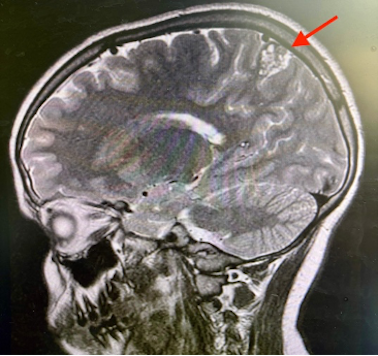

Si impone RM encefalo: lesioni multiple compatibili con cavernomi cerebrali, la maggiore in sede parietale mesiale posteriore sinistra, con segni di sanguinamento subacuto-cronico (Figura 3 e 4).